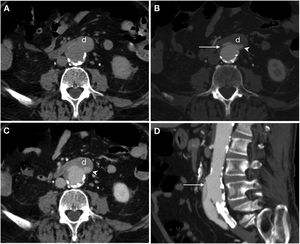

Axial slices from the same patient in Video 2. Computed tomography at baseline (A) and in arterial (B) and portal (C) phases demonstrating loss of the fat plane separating (*) the graft and the third duodenal segment (d) with active extravasation of intravenous contrast towards the duodenal lumen evident from the arterial phase. Reconstruction on the coronal plane (D).

Secondary aortoenteric fistula in a 77-year-old male with a history of aortobifemoral bypass surgery currently presenting an episode of gastrointestinal bleeding with massive haematochezia, abdominal distension and weak distal pulses. Baseline computed tomography (A), in arterial (B) and portal (C) phases and sagittal MIP reconstruction (D) showed an intimomedial tear (arrow) that affected the anterior surface of the graft in contact with the third segment of the duodenum (d). In addition, extravasation of aortic contrast to the gastrointestinal tract (arrow tip) was observed.